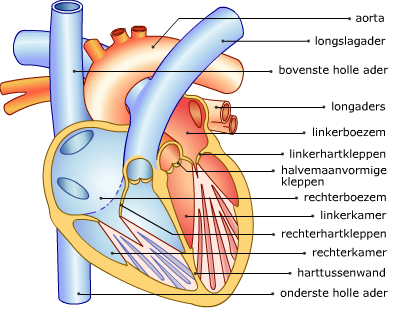

Het hart van binnen

Je ziet hier een schematische afbeelding van een binnenaanzicht van het hart. Leer de namen van de onderdelen die je nog niet kent.